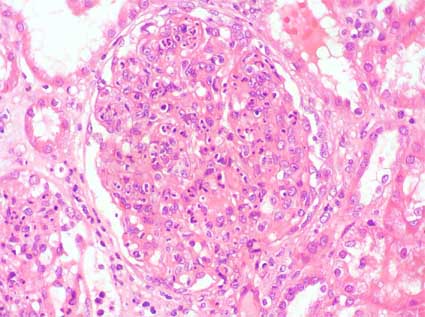

Figura 2.

H&E, X400.